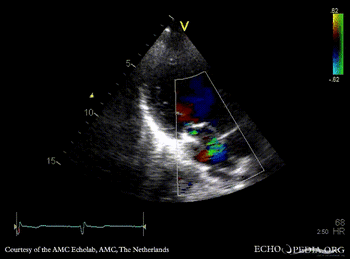

Abnormal pulmonary vein drainage

PLAX: dilated coronary sinus PLAX with Color Doppler: pulmonary vein drainage into coronary sinus, connection with left atrium